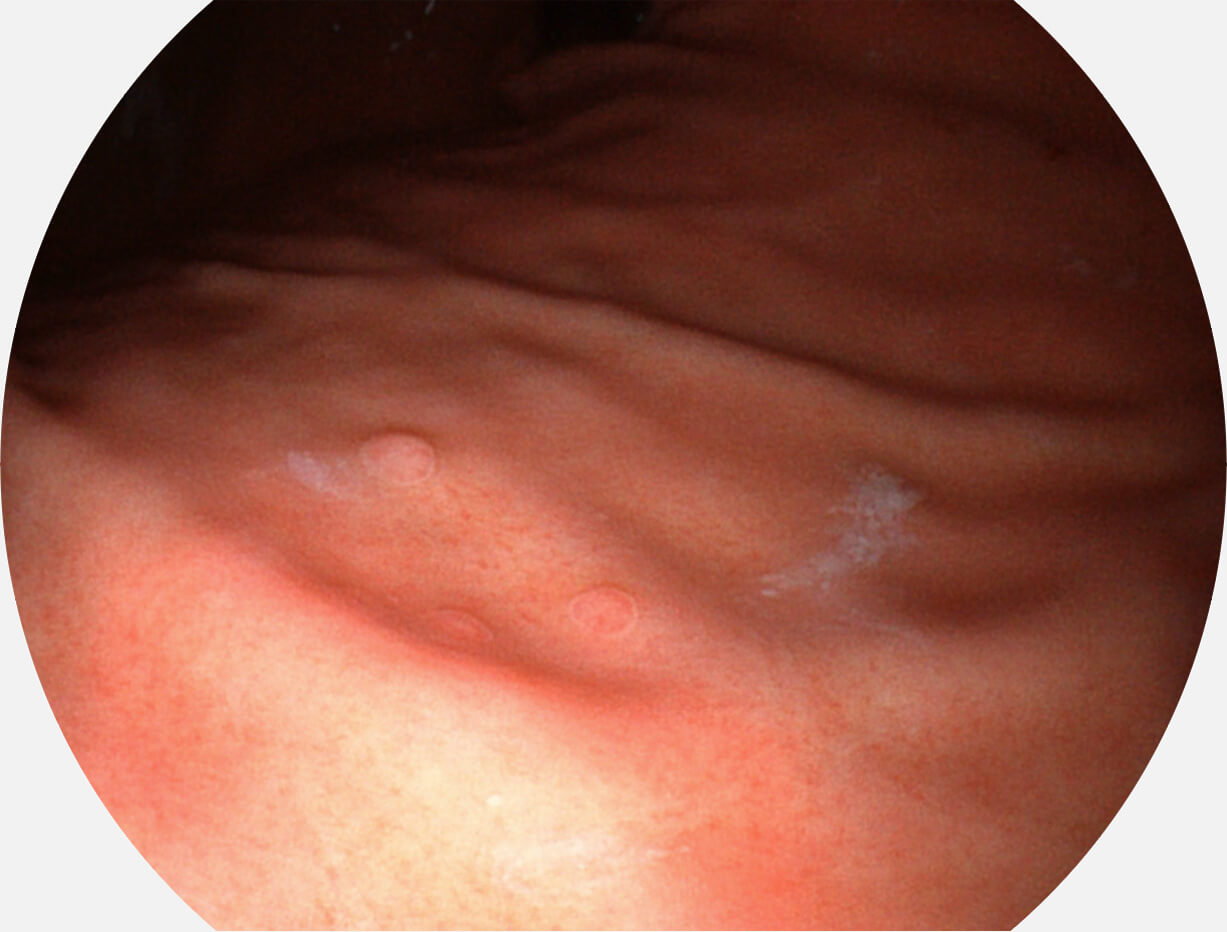

白光图像

SFI图像

Spectral Focused lmaging, SFI

图像具有高亮度、高黏膜血管颜色对比度的特点,且不改变粘液、食物残渣、粪便的基本颜色,可在中远景下进行观察,助力消化道早期疾病的诊断。